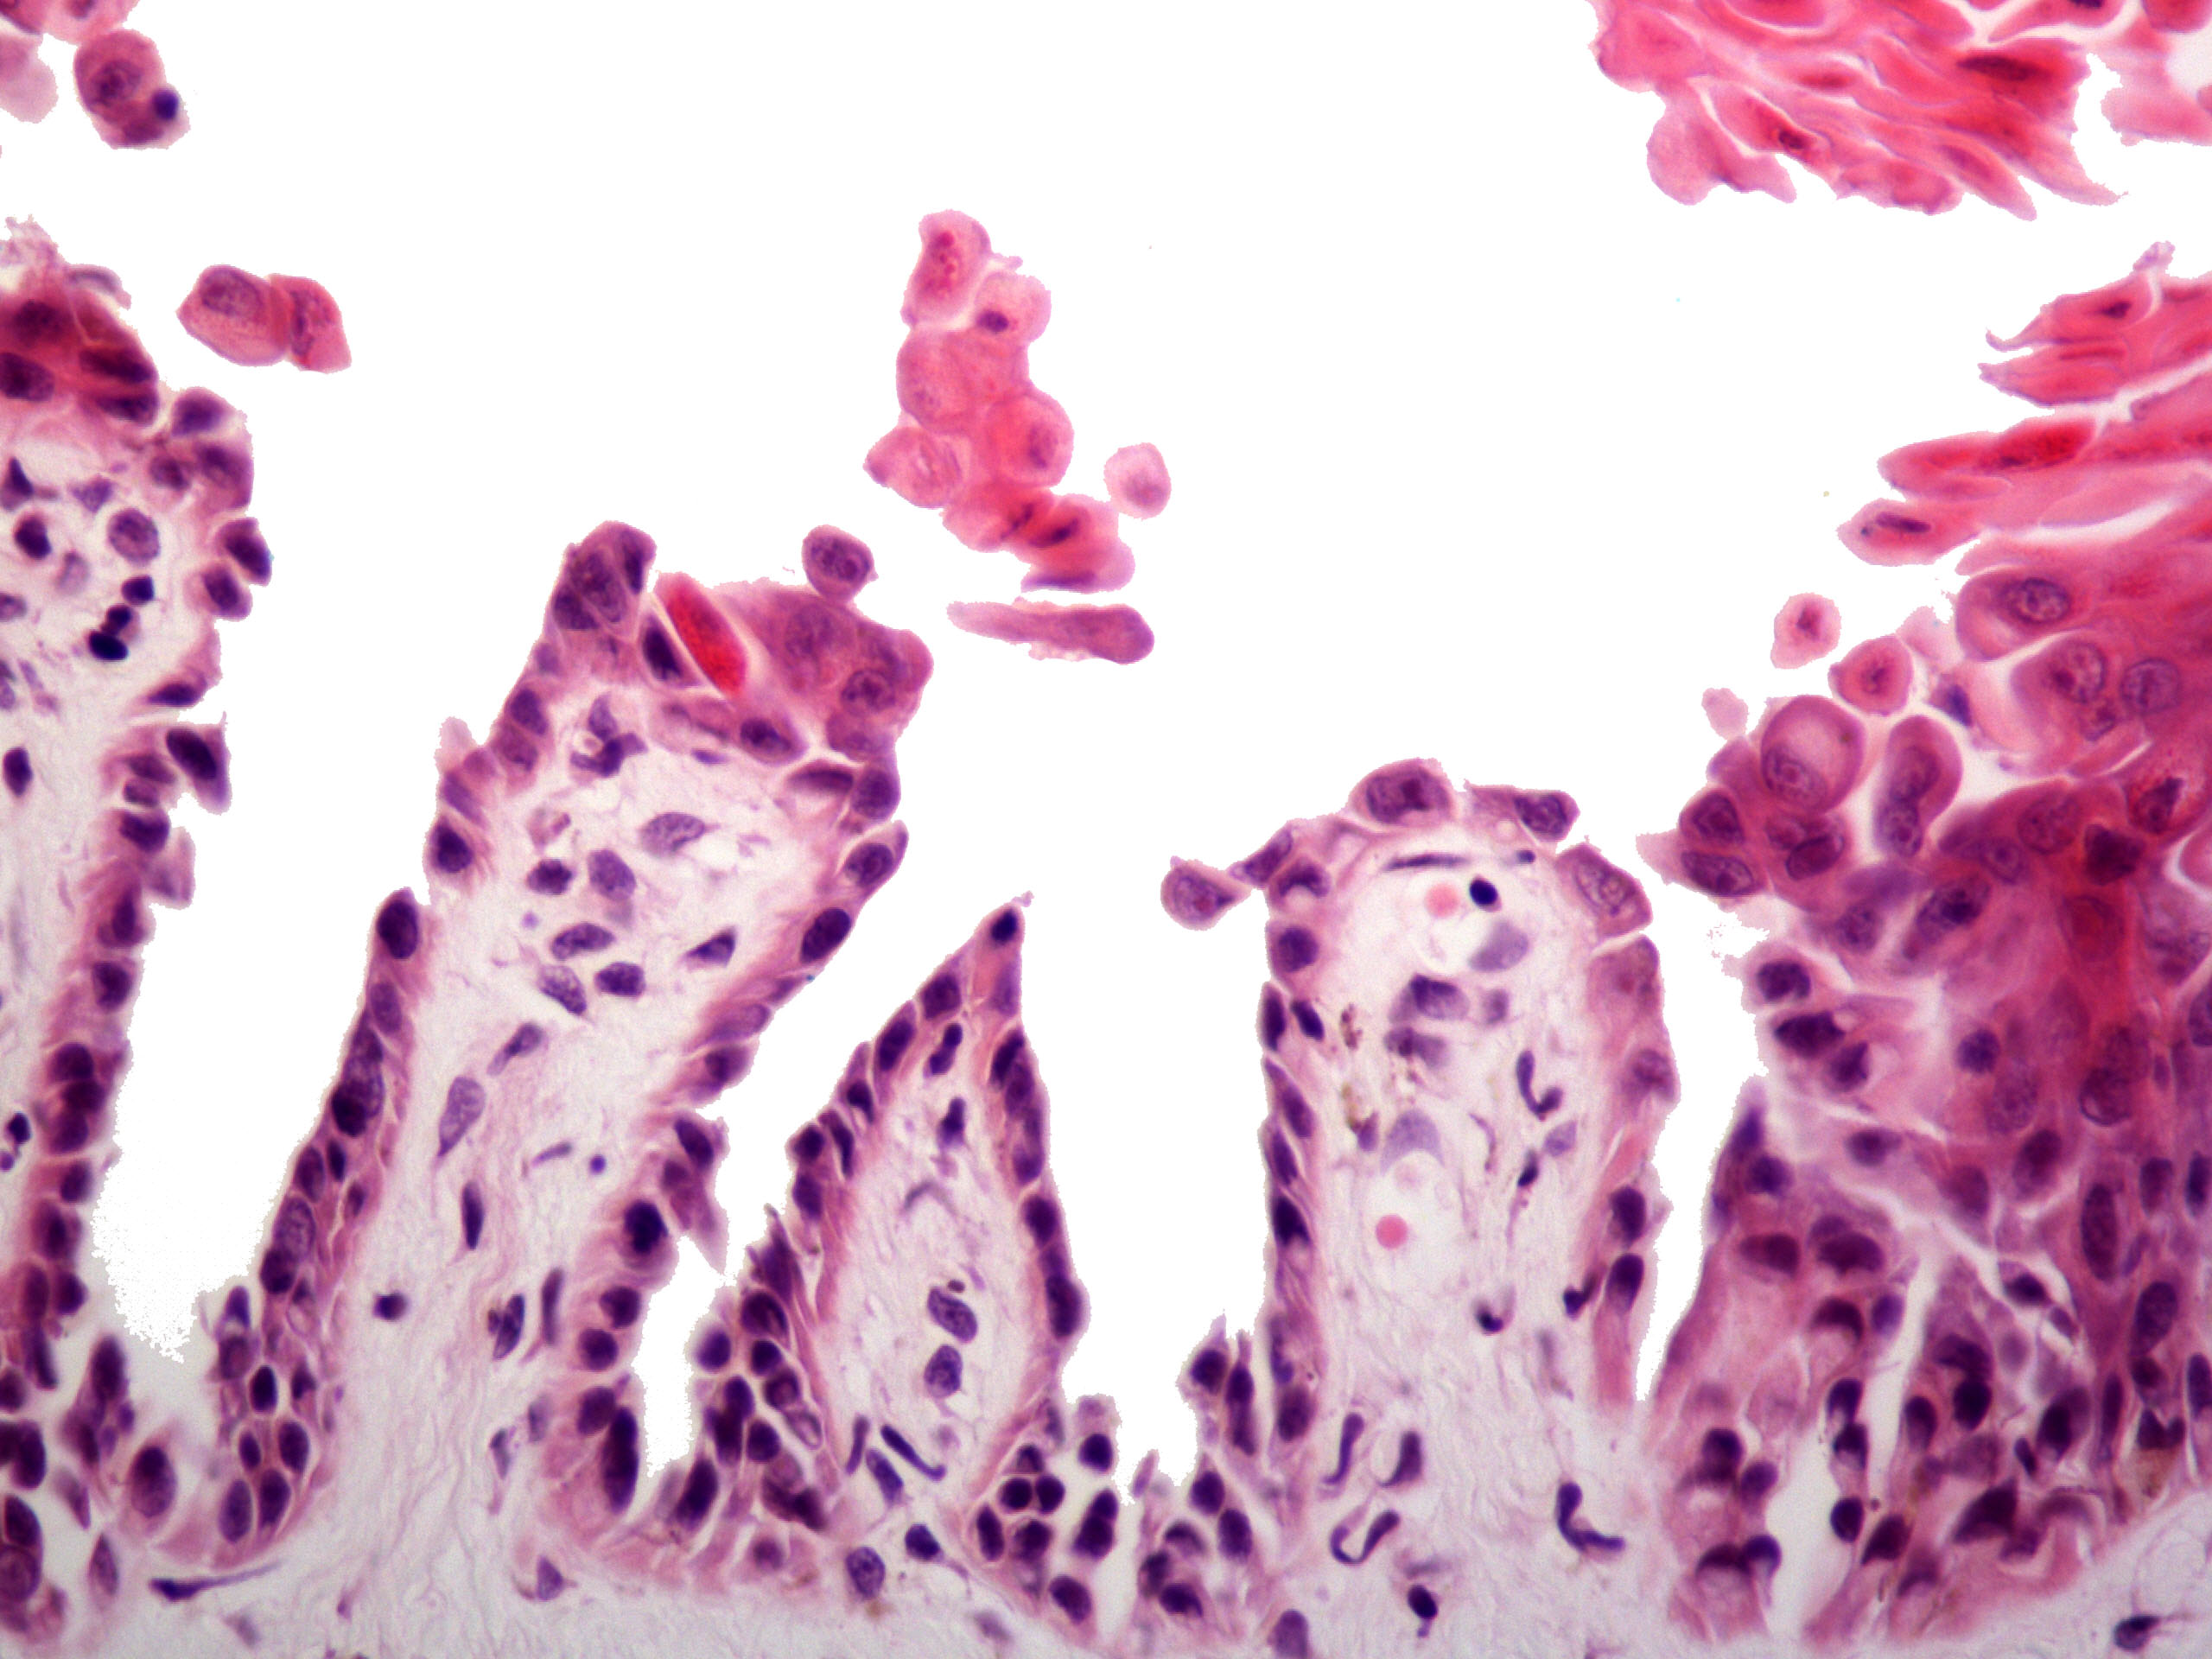

Microscopic (histologic) description

- Parakeratosis

- Acantholysis with characteristic dyskeratosis forming corp ronds and grains

- Corp rond: rounded keratinocyte in superficial spiny and granular layer with basophilic / pyknotic nucleus, perinuclear halo and often a rim of eosinophilic cytoplasm (J Dermatol 2017;44:232)

- Grain: elongated keratinocyte in the stratum corneum with small basophilic nuclei and intensely pink cytoplasm; appears as plump parakeratosis; may form tiers (J Dermatol 2017;44:232)

- Corp rond and grain type dyskeratosis is classical but not specific for Darier disease (see Differential diagnosis)

- Suprabasal acantholysis and clefting with retained single layer of basal keratinocytes overlying dermal papillae which appear to project into the acantholytic cavity (villi) (J Dermatol 2016;43:275)

Microscopic (histologic) images

- Comment: The specimen exhibits parakeratosis, epidermal hyperplasia, acantholytic dyskeratosis with prominent corp rond and grain formation, suprabasal clefting with formation of villi and a mild superficial perivascular lymphocytic infiltrate. Although similar acantholytic dyskeratosis may be seen in a number of entities, given the clinical history of greasy papules in a seborrheic distribution, a positive family history and persistence of lesions, the findings are most consistent with Darier disease.

A. Darier disease. The photomicrograph shows acantholysis with dyskeratosis (corp ronds and grains) as well as the formation of villi classically seen in Darier disease. While Hailey-Hailey disease may have acantholysis with dyskeratosis, prominent corp ronds and grains are lacking. Pemphigus has bland acantholysis and herpes simplex shows distinct viral cytopathic change. Seborrheic dermatitis is a spongiotic dermatitis.